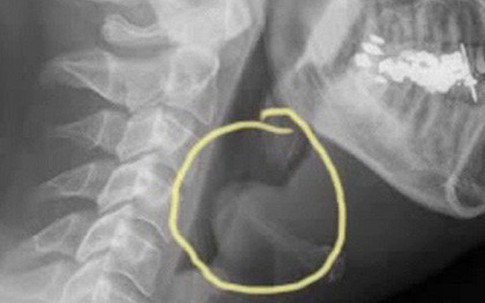

Theo PGS.TS Phạm Thị Bích Đào - Bộ môn Tai Mũi Họng (Trường Đại Học Y Hà Nội), thanh thiệt là sụn hình lá, nằm ở dưới đáy lưỡi, có nhiệm vụ ngăn không cho thức ăn đi lạc vào khí quản khi nuốt. Khi bị viêm nhiễm, thanh thiệt có thể làm bít khí quản và gây tử vong do ngạt thở nếu không được cấp cứu kịp thời.